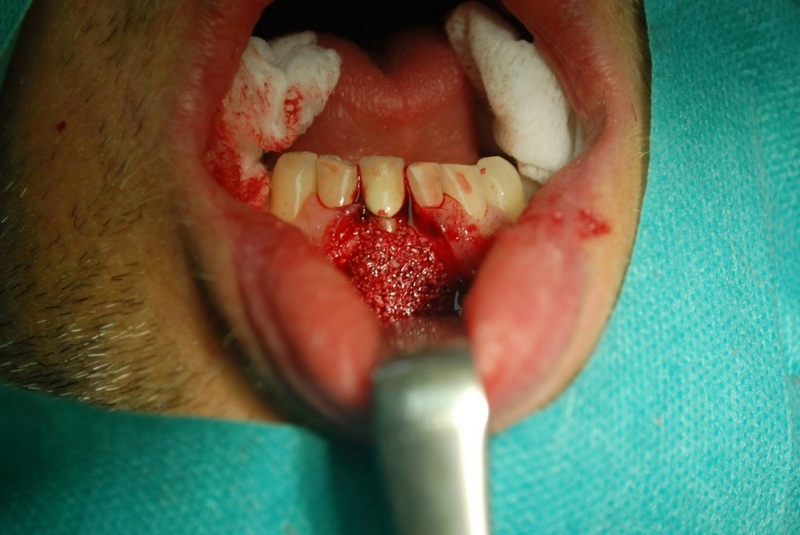

- Implantológia:

1. nadstavba kosti augmentačnými materiálmi (umelé kostné tkanivo, sinus lift a pod.)